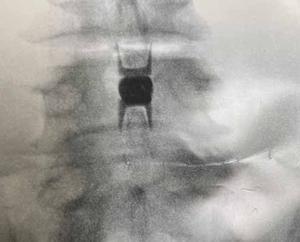

As a safer alternative to traditional, more-invasive surgeries, the Vertiflex procedure involves placing a small implant, or spacer the size of a dime, between the spinous processes of the spine, which are the thin, bony projections on the back of the spine. After the spacer is placed, there is more space for your spinal cord and nerves. The spacer holds the compressed vertebrae further apart which lifts pressure off the nerves to alleviate low back and leg pain.